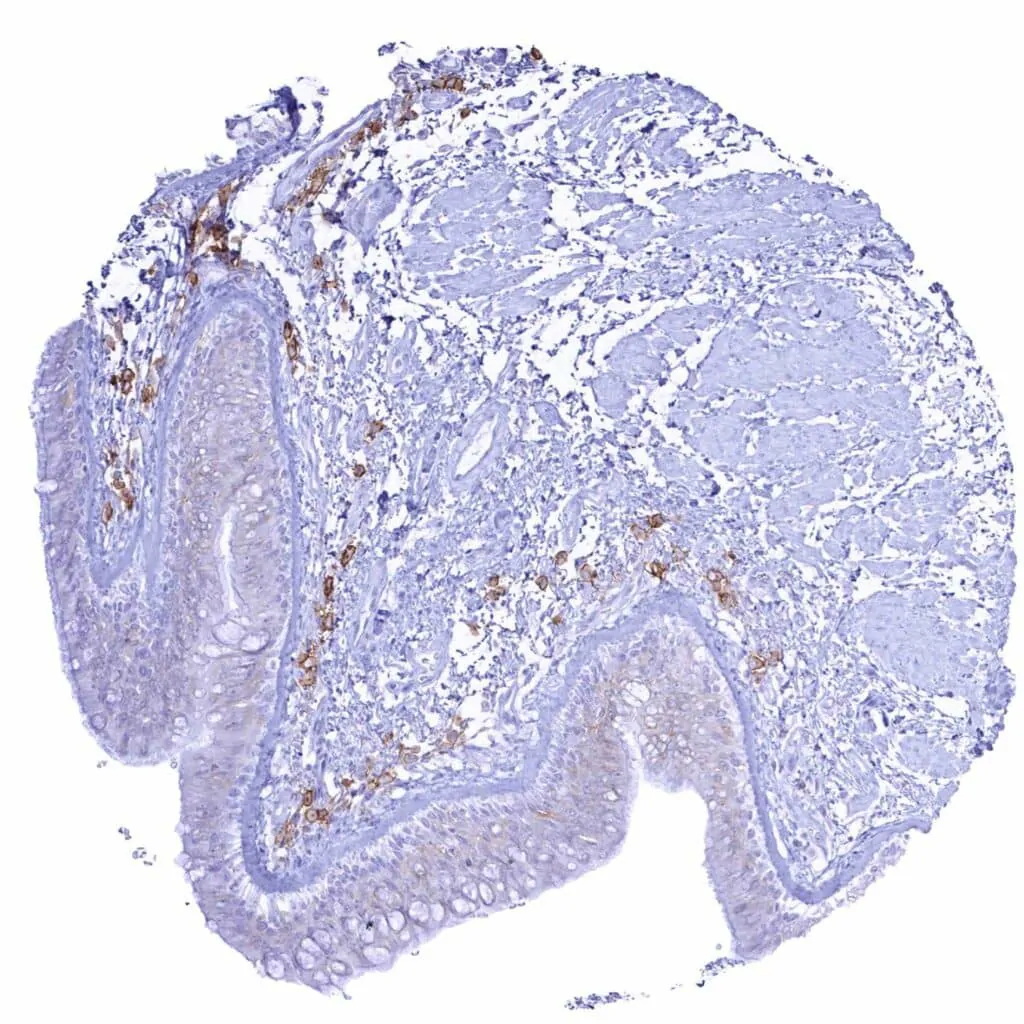

Appendix, mucosa – Strong CD38 staining of a subset of inflammatory cells

Appendix, mucosa